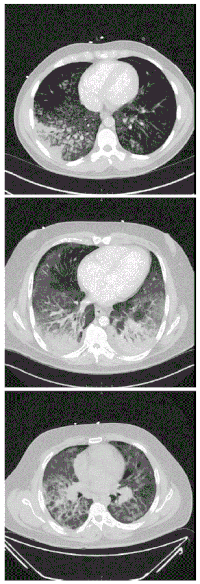

![]() | |

| CT scan of the chest showing diffuse lung infiltrates found in three cases of vaping-associated pulmonary injury | |

There are non-specific laboratory abnormalities that have been reported in association with the disease, including elevations in white blood cell count (with neutrophilic predominance and absence of eosinophilia), transaminases, procalcitonin, and inflammatory markers.[4][59] Infectious disease testing, including blood and sputum cultures and tests for influenza, Mycoplasma, and Legionella were all found to be negative in the majority of reported cases.[59] Imaging abnormalities are typically bilateral and are usually described as "pulmonary infiltrates or opacities" on chest X-ray and "ground-glass opacities" on chest CT.[4]

-

High-resolution computed tomography reveals patchy consolidation, ground-glass opacification in bilateral lower lungs -